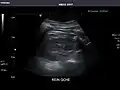

Left kidney -